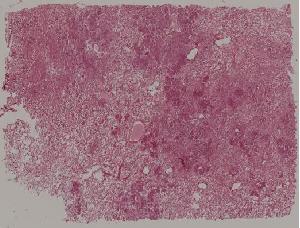

52.小叶性肺炎